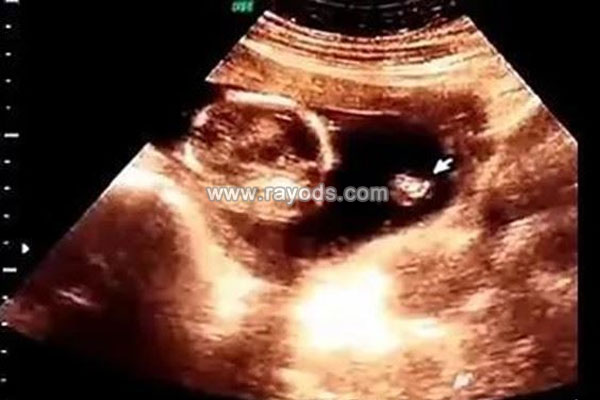

四维3个亮点是男孩昨天去医院做了四维彩超,检查的时间比较久,医生看得非常仔细。中途我看到电脑屏幕上有三个亮点,听人家说做四维有亮点的是怀男孩,也不知道我的这胎是不是男孩。

四维彩超能够看出男女,这是大家公认的事实,也是比较有科学依据的方法。怀孕三个月之后,男胎儿和女胎儿性别分化形成,通过彩超观察胎儿下半身,完全可以看出性别特征的不同。

网传,四维3个亮点是男孩,四维3条白线是女孩。对于这样的说法,医学上没有百分百公认的。换句话说,我们不能肯定,四维单子上有3个亮点,就表示一定是男孩,是女孩的可能性也是有的。从以下过来人分享的经验中,不难看出这一说法还有待考查。

@网妈说:四维彩超单子上,真的男孩女孩的答案,一般怀男孩单子上可以看到3个亮点,胎儿两腿中间有小突起。